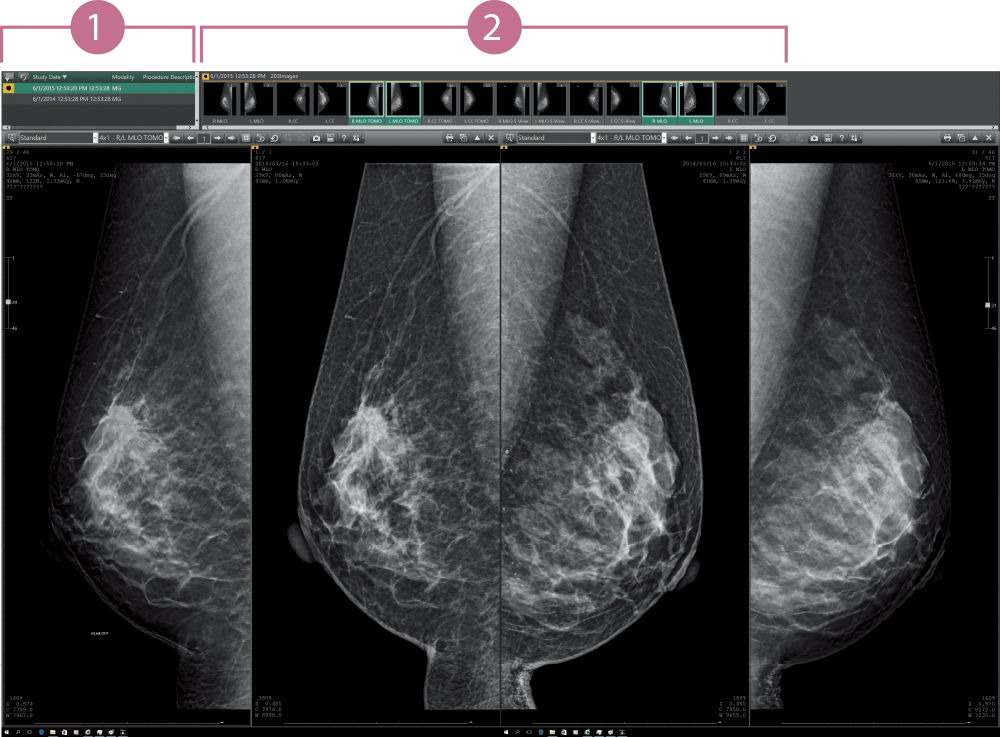

Support for users in conducting diagnosis with reading protocols tailored to mammographic diagnosis and smooth image displays. Customization for reading protocols includes configuration for making comparisons of current and prior images and for S-views synthesized from tomosynthesized images of AMULET Innovality and AMULET SOPHINITY.

The results from multiple exams for a patient are displayed in a list. Users can switch the displayed image with one of the selected images.

The thumbnail window allows users to instantly see all the images taken for each individual exam in a single one view. Each image can be easily selected and displayed by dragging and dropping.

Various images, such as MG, BT, MR, CT, US, etc., are available for mammography diagnosis at the same time.